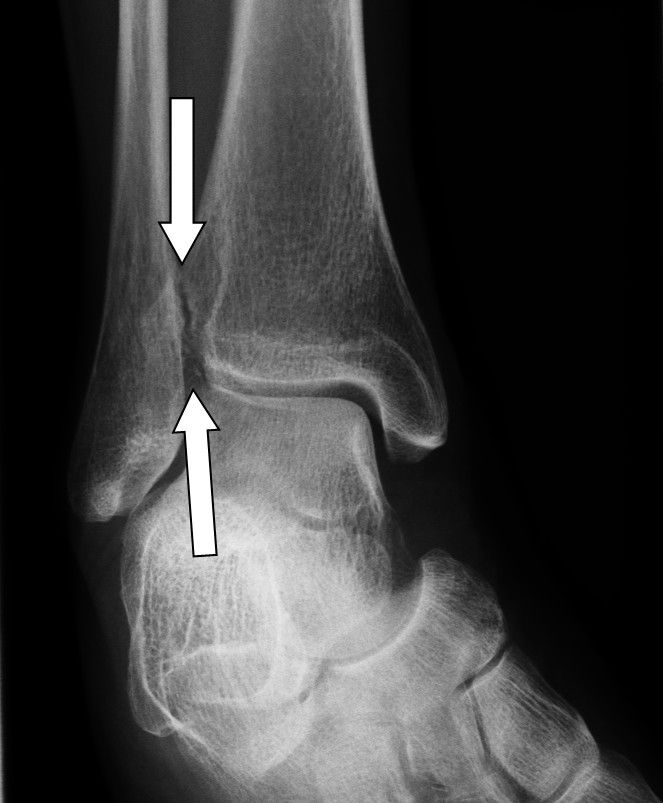

Eine Verschmälerung des Gelenkspaltes im Sprunggelenk weist indirekt auf eine Knorpelschädigung hin und ist damit ein frühes Zeichen der Sprunggelenksarthrose. Resultierend aus dem Knorpelschaden kommt es zu einer Anpassungsreaktion des umliegenden Knochens. Eine Verdichtung des Knochens (Sklerosierung) am Sprunggelenk ist die Folge des Knorpelabbaus.

Zeichen einer fortgeschrittenen Sprunggelenksarthrose im Röntgenbild

Der Gelenkspalt des Sprunggelenkes verschwindet zunehmend und der gelenknahe Knochen verdichtet sich immer stärker. Durch die vermehrte Belastung reagiert der Knochen im Randbereich mit der Ausbildung von Knochenanbauten (sog. Osteophyten). Die Druckzunahme im Knochen kann im Verlauf zu blasenförmigen Knochenauflösungen (sog. Geröllzysten oder Geoden) führen. Dies sind Hohlräume im Knochen, die durch Knochentod (Osteonekrose) entstehen. Als letztes Zeichen einer Sprunggelenksarthrose verformen sich die Gelenkpartner, weil die Belastungslinien des Gelenkes sich verändern.

Am oberen Sprunggelenk flacht das Sprungbein (Talus) häufig ab und der Knochen gleitet nach vorne. Durch diese Veränderungen resultieren zunehmende Einschränkungen, die sich weiterhin auf die benachbarten Gelenke auswirken können.